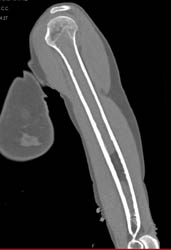

Thigh Hematoma